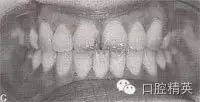

圖9-42 開頜病例矯治后的咬合像

治療:減右上4,右下4,左上6后,直絲弓矯治器+MEAW技術矯治,經2年半治療,擁擠、開頜及反頜畸形得以矯治,咬合關系良好。